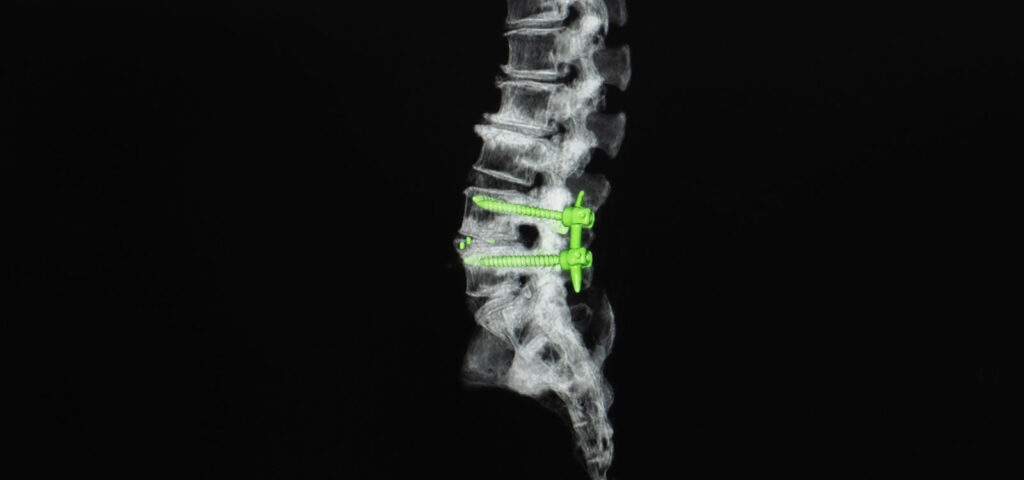

- Pedicle Screws and Rods

- Posterolateral Fusion

- Interbody Fusion

- Posterior Lumbar Interbody Fusion (PLIF)

- Transformational Lumbar Interbody Fusion (TLIF)